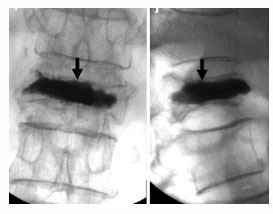

In vertebroplasty procedure, Pain Physicians inject a cement mixture into the fractured bone through a hollow needle in operation theatre under X-ray guidance under local anesthesia. Once cement gets hardened, the patient is free to leave the hospital and can go home on the same day. If the patient needs further observation after the procedure, a short stay in the hospital may be recommended.